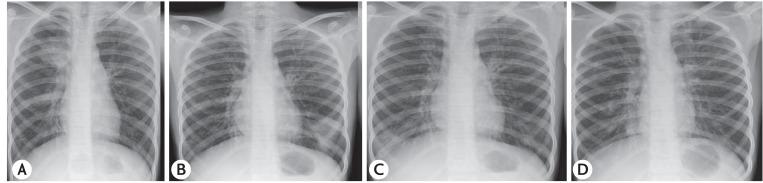

This retrospective review documents the occurrence of pediatric ABPA over a period of 31 years in one unit. Children with asthma, eosinophilia and infiltrates on chest radiograph were screened for ABPA. In these patients, demonstration of immediate hypersensitivity response against species along with serological profile and pulmonary function testing were done. Bronchography/computed tomography (CT) of the chest demonstrated central bronchiectasis (CB). CT of the paranasal sinuses was done in patients with upper airways symptoms. In those suspected with allergic sinusitis (AAS) consent was sought from the parents for the invasive procedure needed for the diagnosis of AAS.

Of the 349 patients with ABPA diagnosed, 42 (12.03%) were in the pediatric age group. The mean age on presentation was 12.9 ± 4 years with a male preponderance. All patients had asthma and positive intradermal/skin prick test against species. Ring shadows, the most common radiological presentation, were seen in 28 of 42 patients. Bronchography/CT of the chest demonstrated CB, a feature pathognomic of ABPA, in 32 of 42 patients. High attenuation mucus plugs was observed in 7 of 36 patients while ABPA-seropositive was diagnosed in 10 of 42 patients. On imaging, sinusitis was seen in 20 of 30 patients with upper airways symptoms of whom eight had suspected AAS. Three parents consented for surgery, which confirmed the diagnosis.